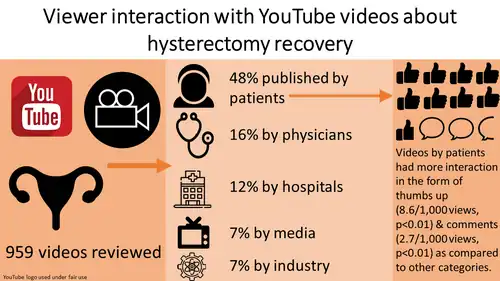

Authors: Ankita Gupta, Kate V Meriwether, Sara Petruska, Sydni Fazenbaker-Crowell, Collin M McKenzie, Adam L Goble, J Ryan Stewart

Objective: We aim to evaluate hysterectomy-recovery related videos on YouTube. [...] Methods: This cross-sectional study analyzed videos available through the YouTube interface. We calculated the views-per-day and interactions (comments, “thumbs up or down”) per 1,000 views for relevant videos. The publishers were categorized into patients, physicians, hospitals, media, industry, nonprofit, government and “other”. Video characteristics were compared between these categories using non-parametric tests. Results: We analyzed 2,092 YouTube videos related to hysterectomy recovery; 959 relevant videos published from August 30, 2006 to June 16, 2017 were included. The largest number of relevant videos were published by patients (48.6%), followed by physicians (15.8%), hospitals (12.7%), media (7.8%), and industry (7.6%). Views per day were similar between videos published by patients and physicians (median 2.1, vs median 2.6, p = 0.31). Videos published by patients had more interaction in the form of “thumbs up” votes (median 8.6/1,000 views, p<0.01) and comments (median 2.7/1,000 views, p<0.01) as compared to other categories. Conclusion: Almost half of the hysterectomy videos on YouTube are posted by patients and have more viewer interaction than other categories. Physicians should consider partnering with patient advocates to improve viewer interaction. doi: 10.15347/WJM/2020.006